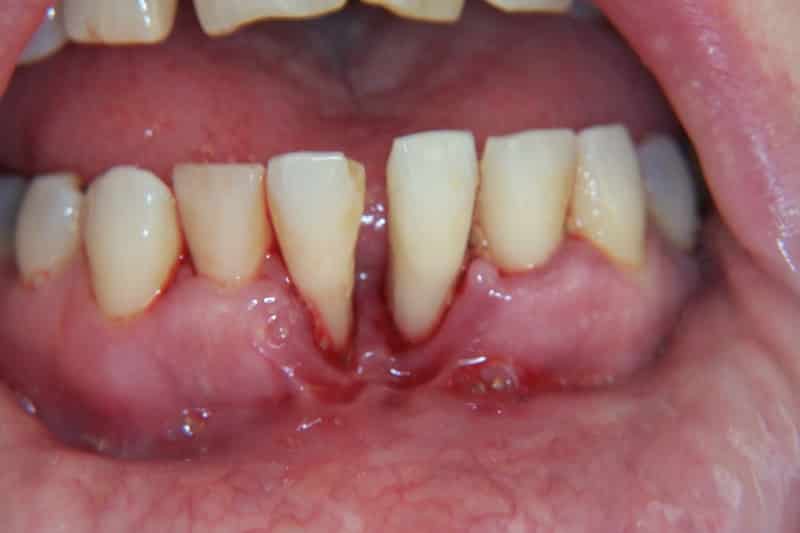

Для отличия пародонтоза от пародонтита существует несколько признаков. Во-первых, пародонтоз является редким заболеванием, в то время как пародонтит распространен. Во-вторых, причиной пародонтоза является нарушение клеточного питания, в то время как пародонтит связан с плохой микрофлорой ротовой полости и наличием зубных отложений. В-третьих, пародонтоз затрагивает альвеолярные отростки всей полости рта, тогда как пародонтит может быть локализованным или распространяться на несколько десен. В-четвертых, при пародонтозе отсутствует воспаление десен, а главным процессом является атрофия, в то время как при пародонтите преобладает воспаление. В-пятых, пародонтоз не сопровождается абсцессами, гнойными выделениями, кровотечениями и патологическими зубодесневыми карманами, в отличие от пародонтита. И, наконец, при пародонтозе зубы начинают расшатываться постепенно, с течением времени, в то время как при пародонтите расшатывание зубов происходит уже на ранних стадиях заболевания.

Диагностика пародонтоза обычно проводится опытным специалистом с высокой точностью. Для установления диагноза используются данные из анамнеза пациента и результаты осмотра полости рта. В начальной стадии заболевания, как правило, отсутствуют симптомы, и только со временем проявляются видимые признаки. Для уточнения диагноза в первых стадиях пародонтоза может потребоваться проведение дополнительных тестов, таких как проба Кулаженко, которая оценивает прочность кровеносных капилляров, и пузырчатая проба, которая измеряет скорость рассасывания отеков на поверхности десны. Считается, что главную роль в развитии пародонтоза играет дистрофия костной ткани в альвеолярных отростках, которая поддерживается различными факторами, такими как плохая гигиена полости рта, слабый иммунитет, наследственность, особенности строения тела и питание. Большинство врачей также считают, что выделение токсинов микроорганизмами является сигналом для развития заболевания, так как бактерии вызывают дегенерацию тканей пародонта на клеточном уровне. Пародонтоз может развиться как во всей челюсти, так и локально. Существуют также научные доказательства роли сосудистого фактора, так как артериальные и склеротические изменения могут влиять на снабжение кровью и питательными веществами тканей пародонта, что приводит к их атрофии. Недостаток витаминов группы C, E, P также может стать причиной развития пародонтоза и ускорить атрофию костных тканей челюсти.